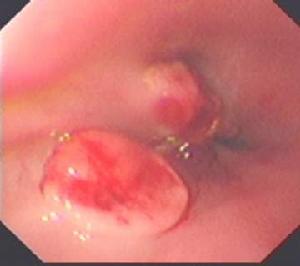

4.容易漏診:幽門管潰瘍行X線鋇餐檢查容易漏診,故走張行胃鏡檢查。胃鏡下可直接觀察到潰瘍的大小、形態及幽門有無梗阻、水腫等情況。

2、胃鏡檢查和黏膜活檢胃鏡檢查不僅可對胃十二指腸黏膜直接觀察、攝影,還可在直視下取活檢作病理和Hp檢測。它對消化性潰瘍的診斷和良、惡性潰瘍鑑別診斷的準備性高於X線鋇餐檢查。在潰瘍太小或太表淺,鋇餐檢查難以發現;鋇餐檢查發現的十二指腸球部畸形可有多種解釋難以確診;活動性上消化道出血是鋇餐檢查的禁忌證,內鏡檢查可確定其來源和性質。鋇餐檢查或內鏡下看似良性的GU中,大約5%實際是惡性的,反之少部分看似惡性的潰瘍,事實證明是良性的,不作活檢難以鑑別。此外,內鏡檢查還可發現伴隨潰瘍的胃炎和十二指腸炎。內鏡下消化性潰瘍多呈圓形或橢圓形,偶也呈線狀,邊緣光整,底部充滿灰黃色或白色滲出物,周圍黏膜可有充血、水腫,有時見皺襞向潰瘍集中。內鏡下潰瘍可分為活動期(A)、癒合期(H)和瘢痕期(S)三個病期,其中每一病期又可分為1和2兩個階段。